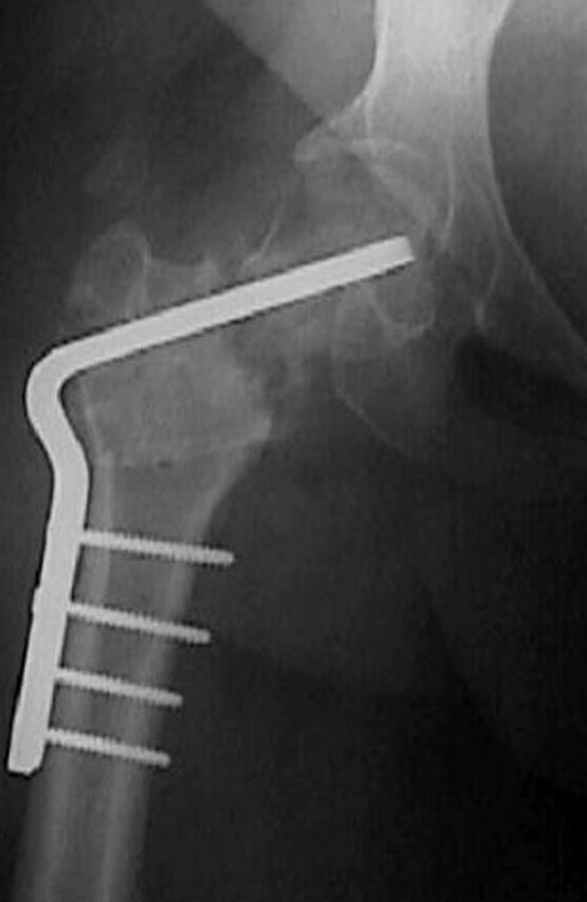

Несколько снимков из моей коллекции, чтобы разьяснить, почему мы до сих пор делаем различные варианты остеотомии.

На рисунке N1 предоперационный план лечения ложного сустава шейки бедра- линия ложного сустава, угол и направление введения импланта, клиновидная остеотомия в градусах и миллиметрах, второй снимок после коррекции, расчет, на сколько удлиняется конечность и размеры импланта;

N3 рисунок окончательный снимок, после операции моя рентгенограмма должен выглядеть примерно как эта картина. На N4 снимке клин перед удалением; N5 послеоперации 3 нед.; N6 окончательная рентгенограмма.